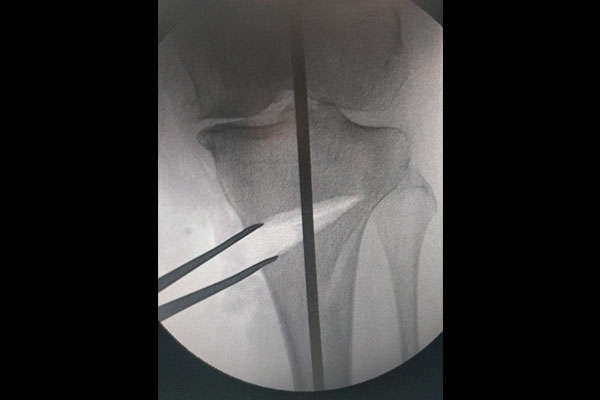

STEPS OF HTO